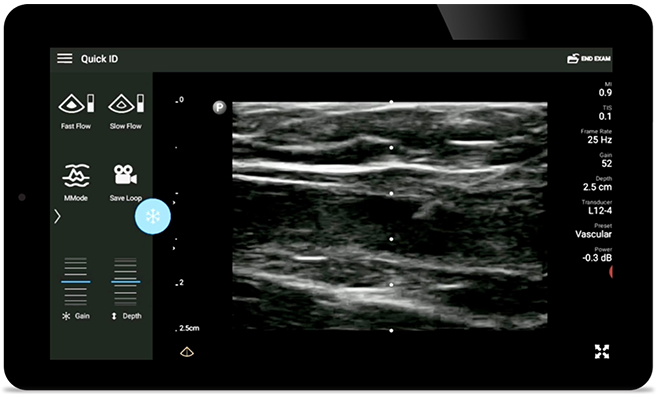

• Rango extendido de frecuencias de operación entre 12 y 4 MHz • Tamaño de apertura: 34 mm • 2D, Doppler orientable a color, Modalidad M, XRES avanzado e imágenes armónicas multivariables, SonoCT • Imágenes de alta resolución para aplicaciones superficiales: tejidos blandos, vasculares, superficiales, musculoesqueléticos y pulmonares • Marcador de línea central • Transductor USB-C con cable reemplazable